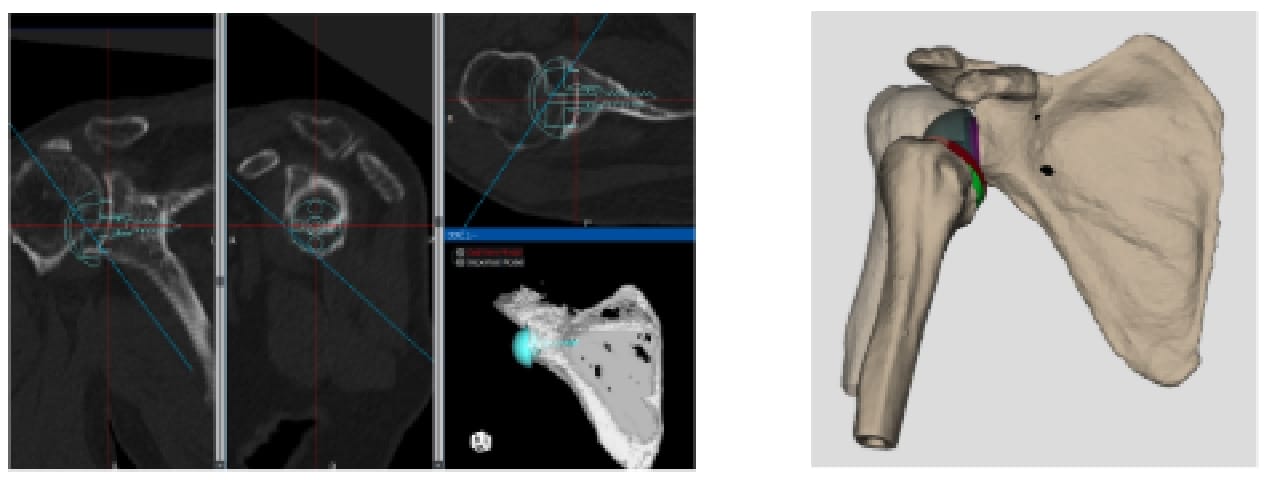

腱板断裂症性肩関節症や修復困難な肩腱板断裂に対しては、リバース型人工肩関節置換術を実施しています。良好な機能回復を得るためには、正確かつ再現性の高いインプラント設置が不可欠です。当班では、CT 画像を用いた術前3Dプランニングに加え、術中ナビゲーションシステムなど最先端の技術を活用することで、より高精度な手術を実現しています。

専用ソフトを用いた術前3Dプランニング